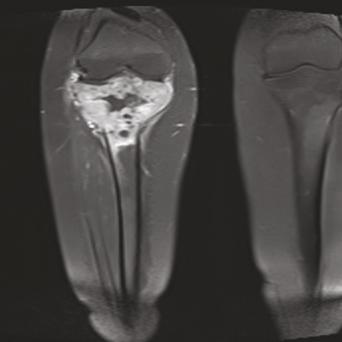

Ostéoporose : quand y penser et quelle prise en charge en MG ?

Avec le vieillissement de la population, l’ostéoporose s’impose comme un enjeu majeur de santé publique. Le dépistage et le traitement doivent devenir systématiques pour les patients ayant des facteurs de risque. Quand penser à l’ostéoporose ? Comment la rechercher ? Quand prescrire une ostéodensitométrie ? Quelle prise en charge selon le profil de la patiente ? Quel suivi réaliser ? Tour d’horizon pour le MG, algorithme décisionnel à l’appui.